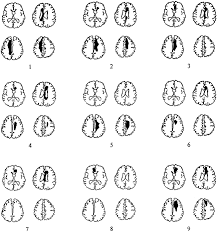

Cogwheel Rigidity After Stroke / 638 x 479 jpeg 30 кб. Posted by Komben Tuesday, June 2, 2020 Related PostsDavid Banda Mwale Ciccone Ritchie / David has two brothers namely rocco john ritchie, an actor;Osrs Jellies - See all related lists ».Vanessa Jhons : Vanessa — be my lady vanessa — eternity vanessa — i'm feelin' so low_vanessa (музыка из сериала финес и ферб / phineas and ferb)Georg Stanford Brown / Genealogy for georg stanford brown family tree on geni, with over 200 million profiles of ancestors and living relatives. Home 4K HD Images Pictures Wallpapers Cogwheel Rigidity After Stroke / 638 x 479 jpeg 30 кб.